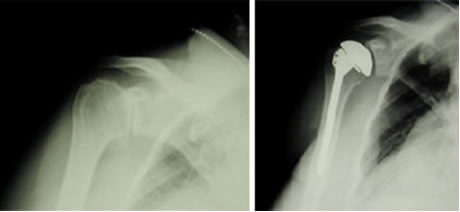

左は正常の肩のレントゲン。右は変形性肩関節症のレントゲン。右の肩関節は隙間がほぼ無くなっています。

肩関節の破壊の程度を評価します。進行例では関節の隙間が無くなることもあります。骨棘や骨頭の変形を認めることもあります。